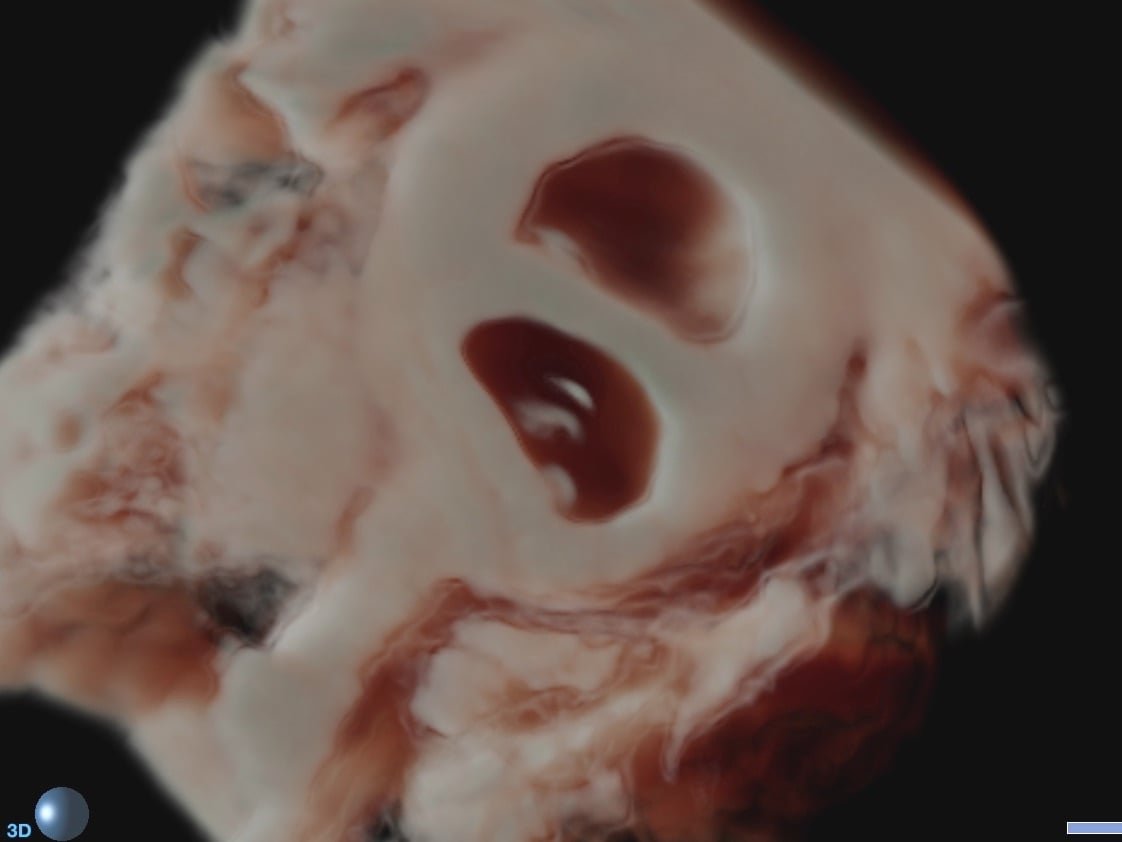

Fetale Echokardiografie, Spezialuntersuchung des kindlichen Herzens

Herzschlag eines Feten im 3. Schwangerschaftsdrittel

Ich arbeite mit einem „High-End-Ultraschallgerät“ der neuesten Generation, welches speziell für Pränataldiagnostik und Frauenheilkunde entwickelt wurde.